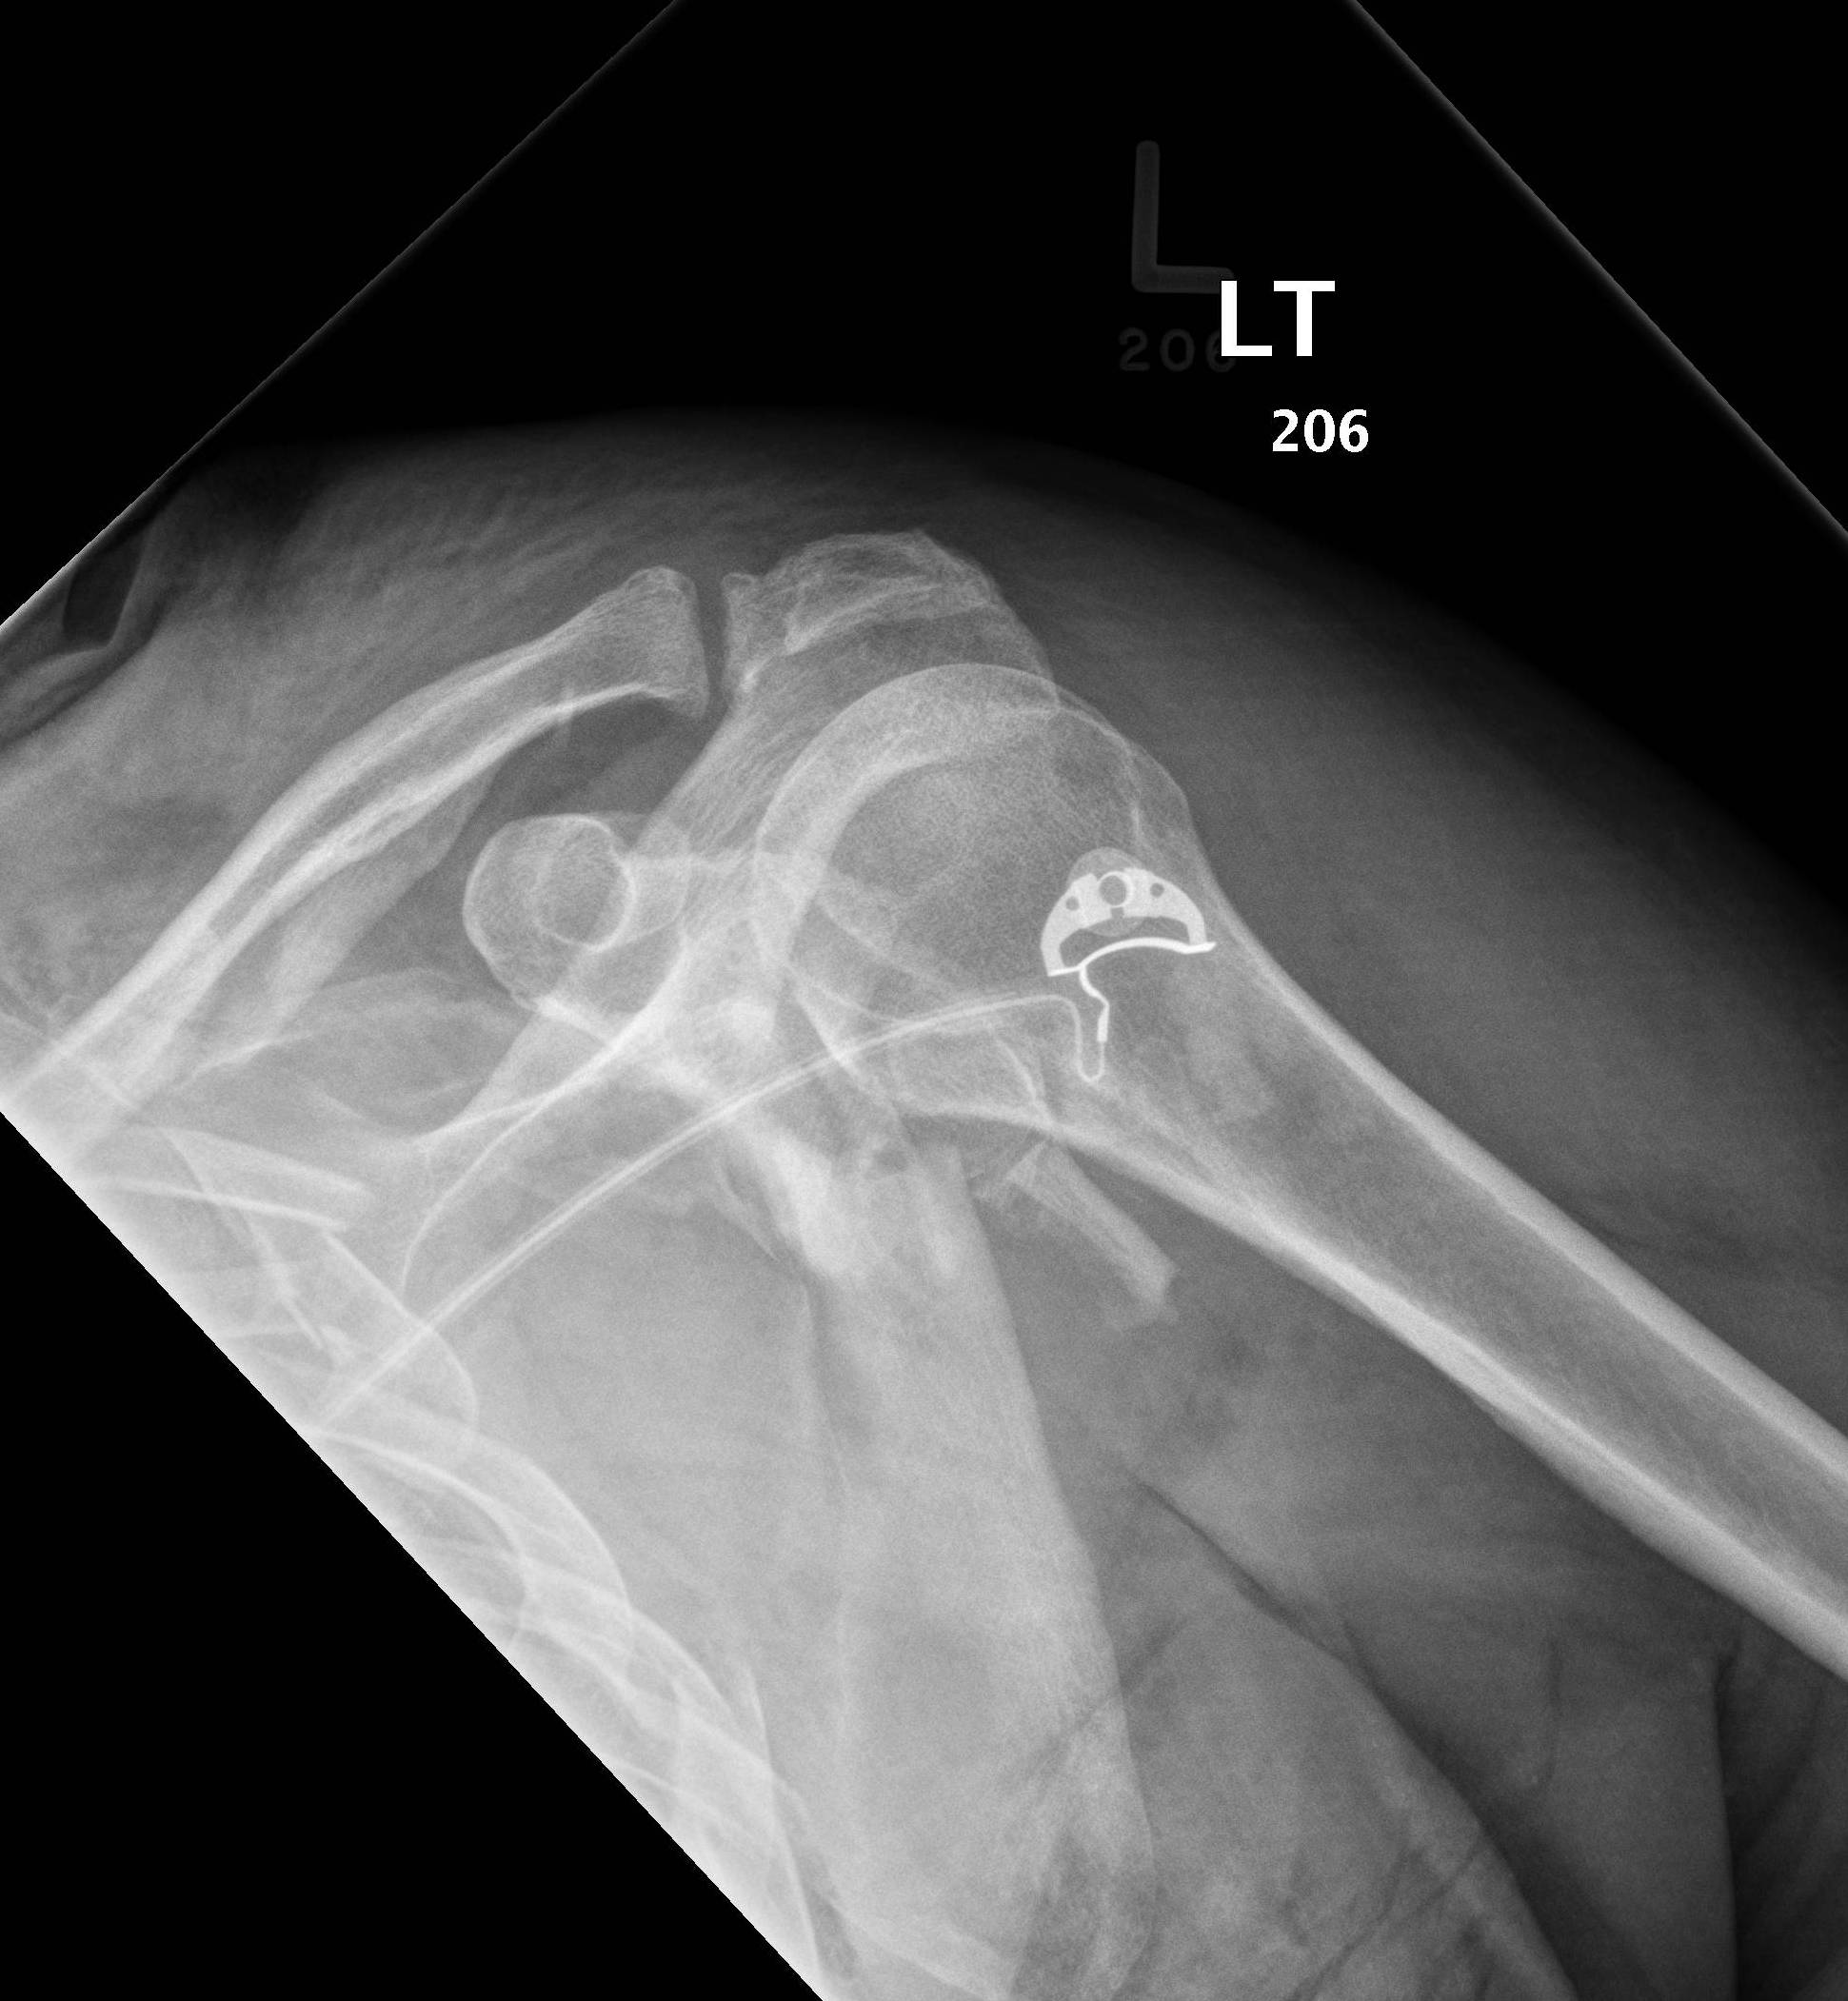

Xray shoulder Fracture posterior half of glenoid with posterior Scapula Bone Fracture The scapula is sturdy and located in a protected place, so. The shoulder blade is often. scapula fractures can be very painful in the shoulder, chest, or back. Fractures of the scapula are most often caused by direct trauma from the back or side. It typically hurts more with breathing or movement of the arm. scapula fractures are. Scapula Bone Fracture.